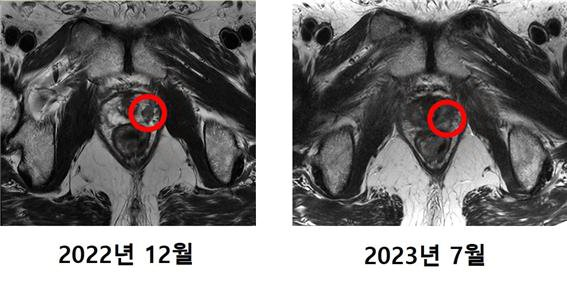

O 방사선 치료는 전자기(감마선, x선 등) 방사선을 이용하던 데서 치료 효과를 높이면서 부작용을 최소화하는 입자(양성자, 중입자) 방사선으로 진화하고 있다. 입자 방사선은 암에 닿기 전까지 방사선을 거의 방출하지 않고 암에서 80%가량을 방출하는 '브래그 피크'(Bragg Peak)라는 특징이 있어 부작용은 적고 효과는 강력하다. 국립암센터, 삼성서울병원에 양성자 치료가 도입됐고 세브란스병원은 최근 중입자 치료를 통해 전립선암 2기 환자 치료를 성공적으로 끝마쳤다. 한 주에 3~4회씩 총 12번 치료를 받은 결과 전립선특이항원(PSA) 수치는 0.01ng/㎖ 미만으로 떨어졌고 MRI 촬영 결과 암 조직이 발견되지 않았다. 주변 장기의 피해도 없어 치료 후 일상생활을 무리 없이 지내고 있다.